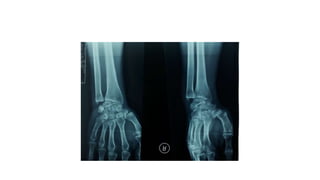

• #35 Ulnar shortening osteotomy. A, Wrist of 16-year-old male wrestler with bilateral ulnar wrist pain and positive ulnar variance of 2 mm. B, Four weeks after surgery, wrist is in ulnar neutral variance and osteotomy is healed.